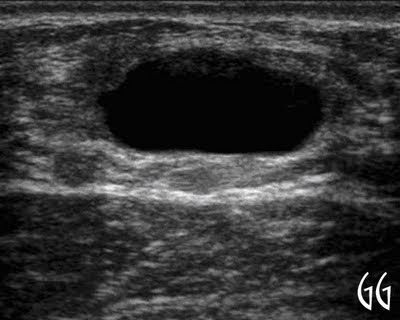

Quiste Simple de Mama

Caso Clínico Mujer de 27 años de edad, acude a consulta con historia de bulto en mama izquierda de aproximadamente 15 días de evolución,...